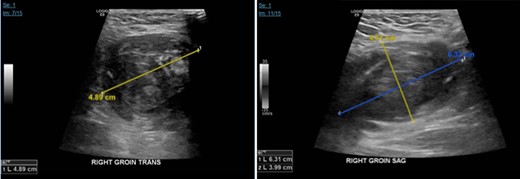

On the following day after the right transfemoral access approach, patient presents to ED with R groin and scrotal pain. On evaluation, severe tenderness on the R groin and scrotum was noted associated with worsening swelling and ecchymosis (Fig. 1). Vitals were within normal limits and initial hemoglobin of 12 g/dl. Ultrasound of the right groin showed a 6.3 × 4.0 × 4.9 cm hematoma (Fig. 2), his duplex ultrasound of bilateral testicle showed diminished blood flow on the right compared to the left (Fig. 3). CT of the pelvis revealed a pseudo-aneurysm on the R groin originating from the common femoral artery (CFA) measuring 2.5 × 1.4 cm and extending into the R inguinal canal, filled with hemorrhage and extension into the R scrotum that measures 13.7 × 6.4 × 6.6 cm (Fig. 4). During his clinical course, he has been hemodynamically stable in spite of drops in daily hemoglobin from 12, 8.9, 6.9, 5.9 g/dl, respectively, requiring two units of blood transfusions on hospital Day 3, and achieving a rise in hemoglobin to 8.6 g/dl. Patient then underwent an ultrasound-guided thrombin injection of the pseudo-aneurysm by the interventional radiologist without any complications and without any evidence of recurrence on ultrasound on the following day. Urology was consulted and offered no urologic interventions as his symptoms were improving. The scrotal and groin hematoma subsequently decreased in size. Patient was discharged on hospital Day 6 with aspirin and Plavix. Patient was followed up in clinic with no complains. On exam, there was a decreasing scrotal and R groin swelling/ecchymosis and improvement of penile swelling.

Ultrasound of the right groin showing 6.3 × 4.0 × 4.9 cm hematoma.